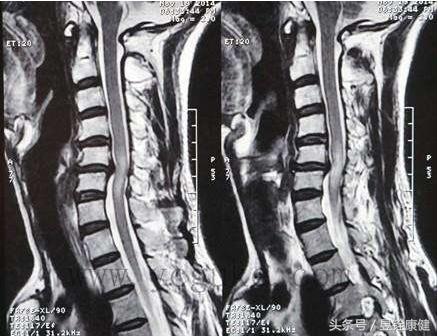

脊髓型颈椎病MRI征象